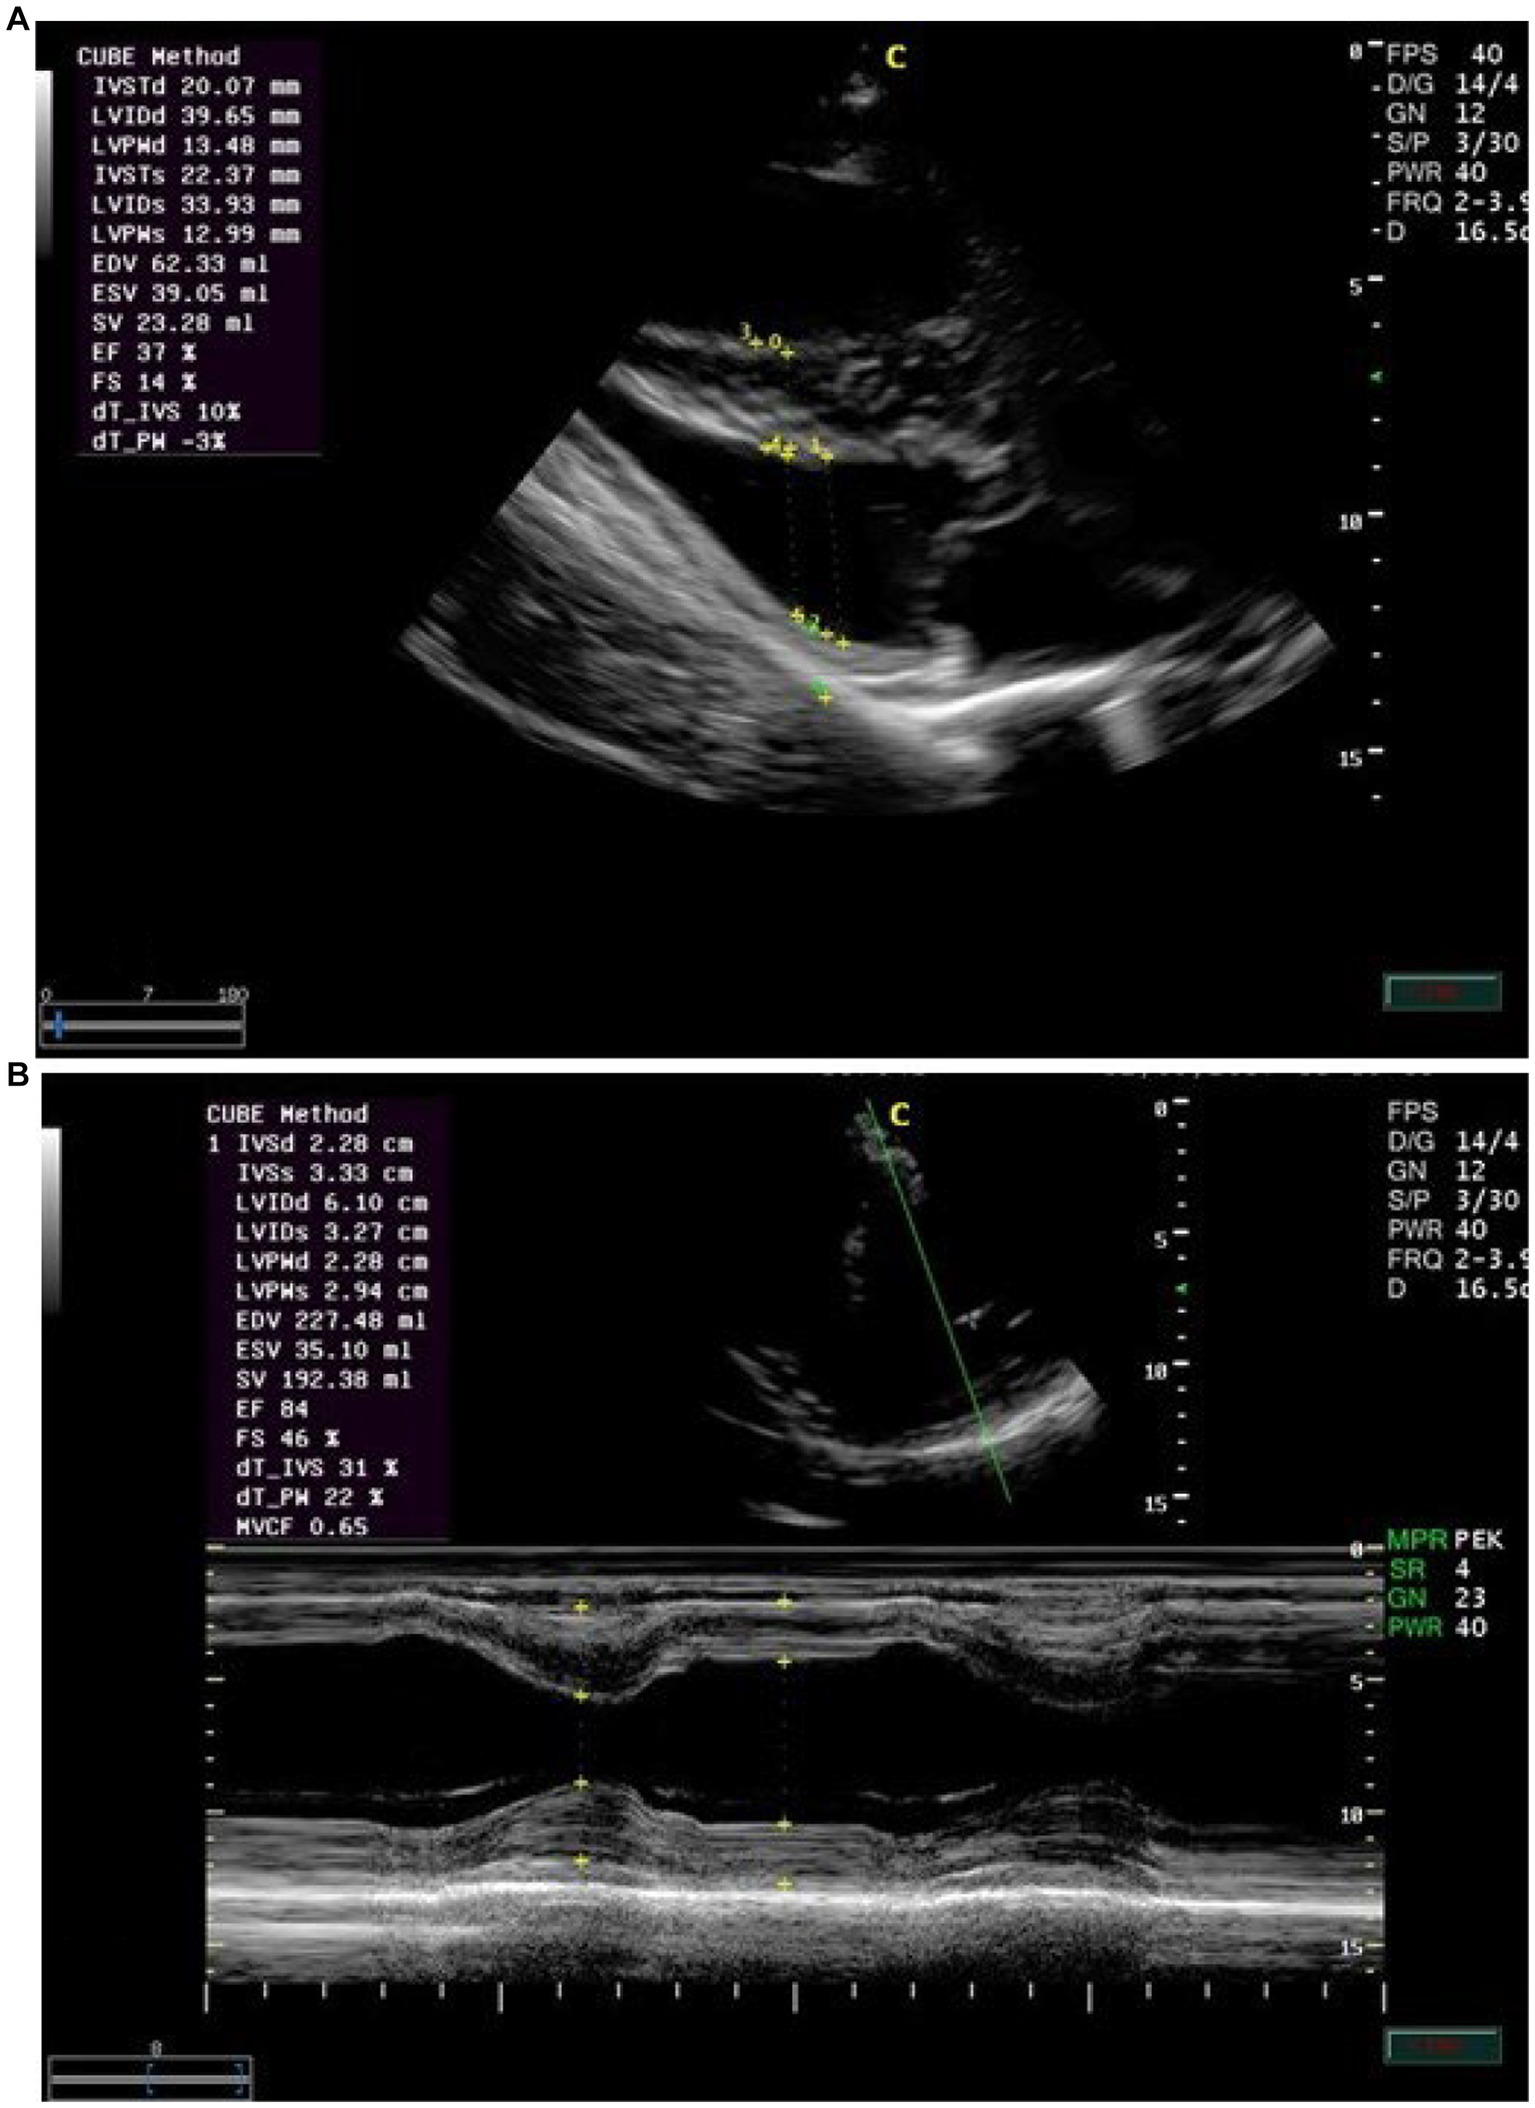

Echocardiographic findings were recorded to assess the left ventricular images (Figures 1A,B), mitral valve (Figure 2A), and aortic valve (Figure 2B) images in the examined donkeys. The effects of time, treatment, and time x treatment interaction after administration of metoclopramide and ondansetron in the investigated donkeys are presented in Tables 1–5. In general, FS% was significantly affected by the time for metoclopramide (p = 0.031) and ondansetron (p = 0.047) compared with placebo. However, treatment with metoclopramide provoked significantly higher percentages of FS at T60 (p = 0.009) and T90 (p = 0.028) compared with those of ondansetron and placebo. The time x treatment interaction also showed statistically significant alterations of FS% (p < 0.05), while values returned to the basal line at T240 (Table 1). Other cardiac dimensions, namely IVS, LVID, and LVPW at end-diastole and end-systole, EDV, ESV, and SV, and cardiac indices such as EF, showed no significant (p > 0.05) variation among the examined donkeys.

Figure 2

(A) The right parasternal long-axis view of the left ventricular outflow tract of the mitral valve in examined donkeys using M-mode echocardiography at zero time. IVS = interventricular septum; LV = left ventricle; LVW = left ventricular wall; MV = mitral valve. (B) The right parasternal long-axis view of the left ventricular outflow tract view of the aortic valve in examined donkeys using M-mode echocardiography at zero time. RA = right atrium; AO = aorta; AOV = aortic valve; LA = left atrium.